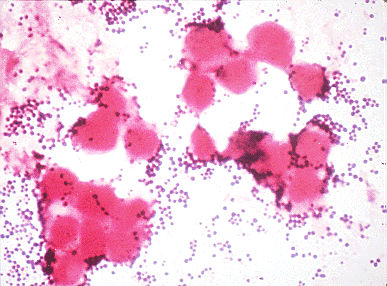

| An image of Staphylococcus

aureus as seen through a microscope. Almost all S. aureus

are resistant to penicillin, however, most are still susceptible to

Vancomycin. Image from University

of Texas Medical School. |